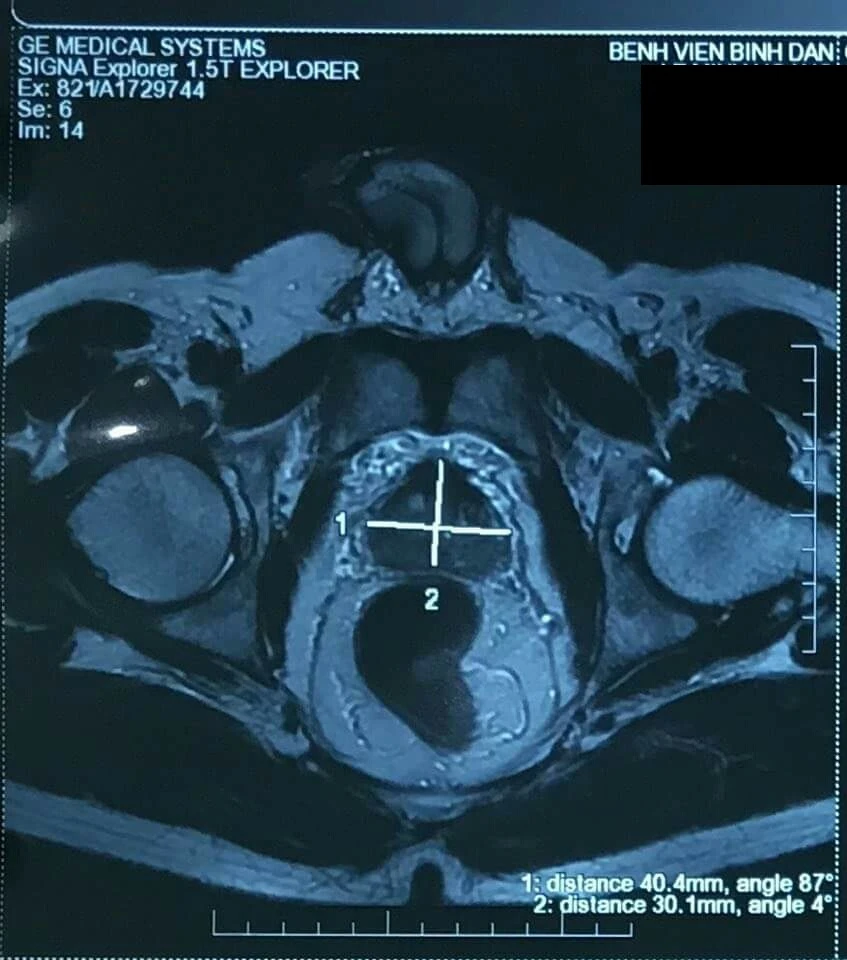

Trước đó, trong một đợt tầm soát sức khỏe vào tháng 10-2017, ông D. được các bác sĩ khoa Tiết niệu BV Bình Dân phát hiện bị ung thư tuyến tiền liệt. Ngoài ra, chụp cộng hưởng từ (MRI) cho thấy khối choán chỗ lan toàn vùng ngoại biên, chưa xâm lấn túi tinh hai bên, chưa xâm lấn vỏ bao. Kết quả xạ hình xương cũng chưa ghi nhận bất thường.

Hình ảnh khối u tiền liệt tuyến của ông D.